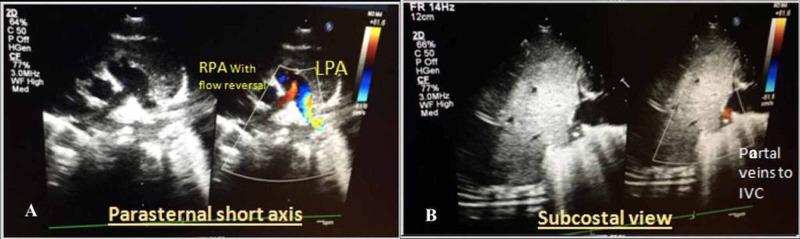

Scimitar syndrome is a relatively uncommon association of congenital cardiopulmonary anomalies characterized by partial or complete anomalous pulmonary venous drainage from the right lung. It can present in the neonatal period, as well as later in life. In this paper, we present a case of a 15-day-old Saudi boy diagnosed with scimitar syndrome who presented with a chest infection and respiratory distress, along with a brief review of the literature. Key diagnoses, such as chest x-ray, echocardiography, and computerized tomography of the chest, led to the conclusion that the patient was a rare scimitar syndrome case. Understanding that scimitar syndrome usually presents with variable symptoms, we had to perform several diagnostic tests before concluding this was a scimitar syndrome case. Infantile scimitar syndrome requires a high degree of suspicion for early referral and management, so we needed to conduct a special diagnostic test. Our literature review of scimitar syndrome has supported our findings and encouraged us to share this rare scimitar syndrome case.

弯刀综合征是一种相对罕见的先天性心肺异常组合,其特征为右肺部分或完全性肺静脉异位引流。它可在新生儿期出现,也可在生命后期出现。在本文中,我们报告一例15日龄沙特男婴,诊断为弯刀综合征,该患儿因胸部感染和呼吸窘迫就诊,并对相关文献进行简要综述。胸部X线、超声心动图及胸部计算机断层扫描等关键诊断手段得出结论,该患者为罕见的弯刀综合征病例。鉴于弯刀综合征通常表现出多种症状,我们在确诊该病例为弯刀综合征之前进行了多项诊断检查。婴儿期弯刀综合征需要高度怀疑以便早期转诊和治疗,因此我们需要进行一项特殊的诊断检查。我们对弯刀综合征的文献综述支持了我们的发现,并鼓励我们分享这一罕见的弯刀综合征病例。